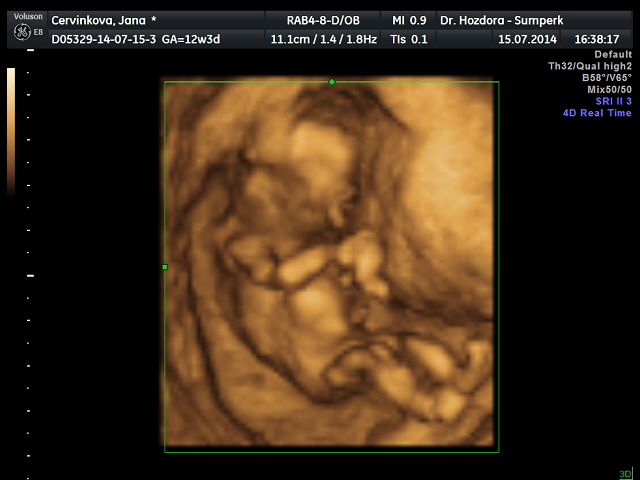

Děvčata,tak jsem doma z ultrazvuku,ten dopadl skvěle,šíjové projasnění,nosní kůstka,vše tak,jak má být. Dnes jsem 12+3,ale podle ultrazvuku už 13+1. Vypadá to pravděpodobně,že čekáme holčičku,ale jistější to bude ve 20.tt. Zítra mi sestry zavolají,jak dopadly krevní odběry...zatím mám z toho skvělý pocit. A docela mimo je i můj chlap,moc se nevyjadřoval,on ty pocity dusí v sobě,ale vypadal spokojeně. Tak zítra se screening zkompletuje a věřím,že to bude v cajku. Určitě dám zítra vědět..